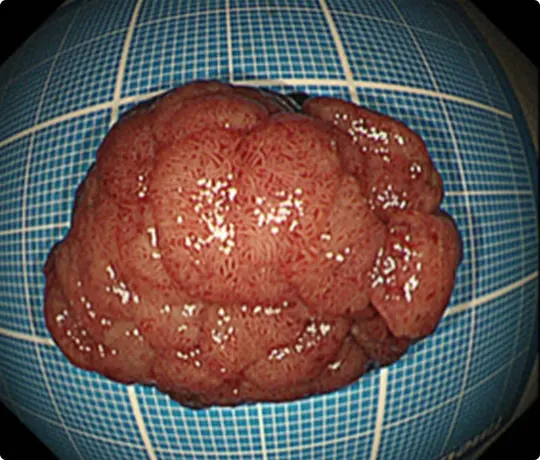

切除した検体です。病理検査で早期大腸がんと診断されました。がんは完全に切除されており、治癒と判定されました。